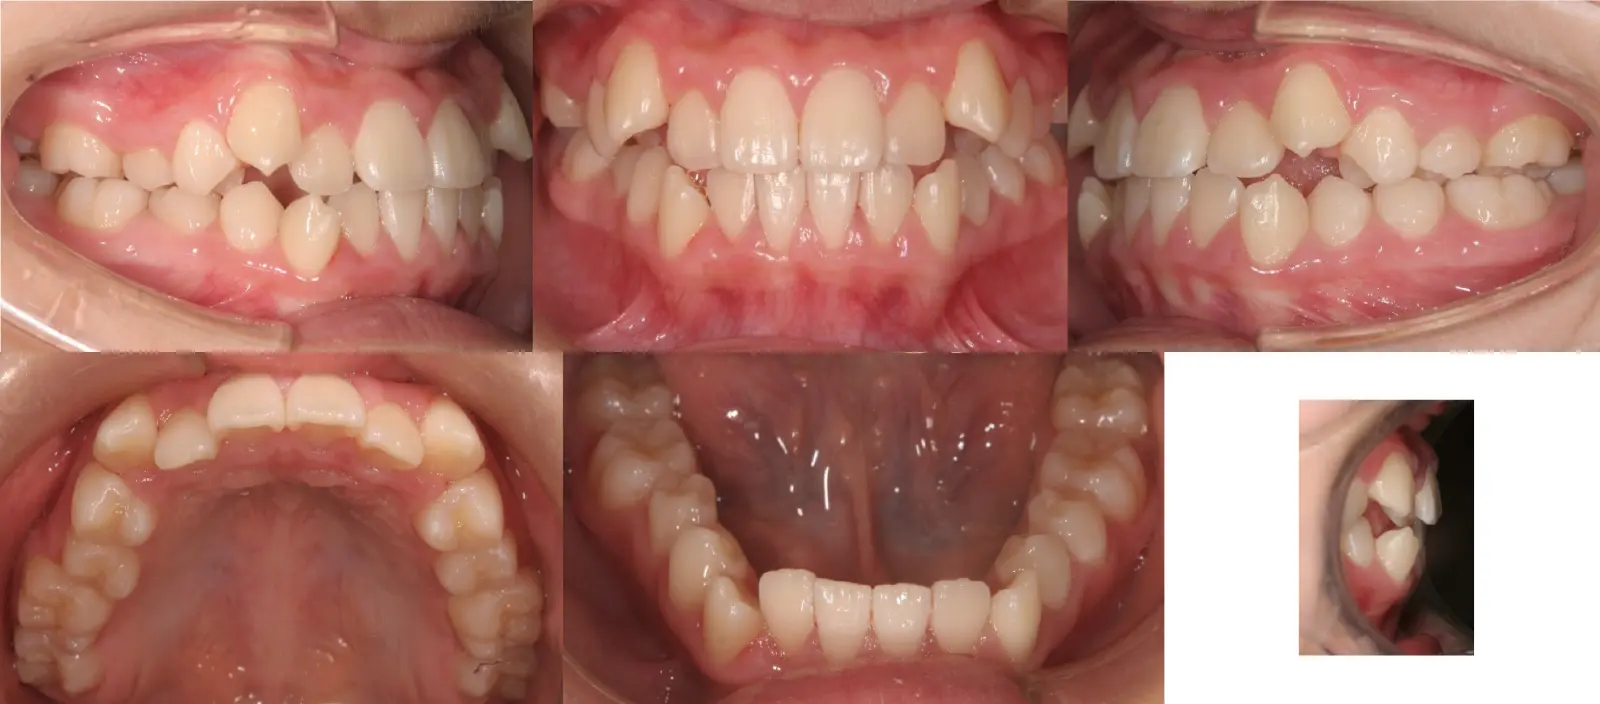

叢生

乱杭歯、八重歯

- 年齢

10代

- 治療期間

1年8ヶ月

- 治療回数

19回

- 治療に用いた主な装置

カスタムメイド型マルチブラケットタイプのデジタル矯正装置(インシグニア)

- 治療費

600,000円(税別)、調整料5,000円(税別)

※伊那分院にて治療

- 抜歯部位

上顎第一小臼歯2本

下顎右第二小臼歯1本、左第一小臼歯1本